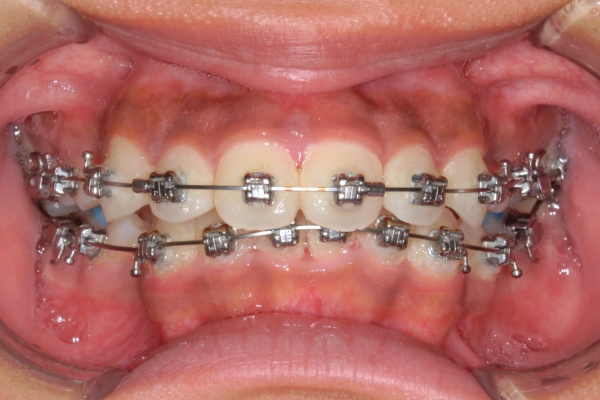

PROCESS

半年

上顎前歯が1 cm近く前方に出ており、叢生を改善しつつ前歯を大きく引っ込めるために上下顎小臼歯の抜歯が必要と診断しました。治療では奥歯の噛み合わせのズレも整え、治療後は前歯でも奥歯でも食べ物が噛みやすくなったと、患者さまに非常に満足していただけました。